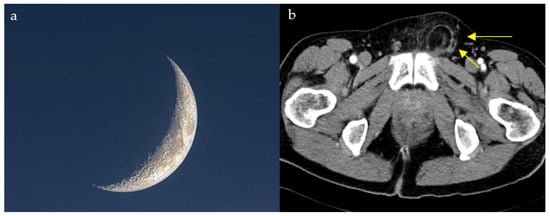

Cosmic Signs in Radiology: A Pictorial Review

Pattern recognition remains a cornerstone of radiologic interpretation, as it facilitates a confident and comprehensive differential diagnosis. Certain pathologies present with specific and highly recognizable patterns on imaging modalities. These patterns can resemble familiar real-life phenomena, including cosmic bodies that surround us. We present in this article a compilation of radiologic signs across various modalities that take inspiration from cosmic phenomena. For each sign, we summarize its defining imaging appearance, typical clinical context, and common pitfalls; where available, we note diagnostic performance (e.g., sensitivity/specificity) to guide appropriate weighting in practice. By coupling memorable imagery with succinct clinical guidance, this pictorial review aims to support a faster, more accurate pattern recognition that is applicable in both low-resource and tertiary care settings, while recognizing that these signs function as educational aids rather than validated diagnostic tests. In familiarizing themselves with these classic signs, training radiologists can benefit from an engaging and memorable way of recognizing various pathological conditions. Full article

Figure 1